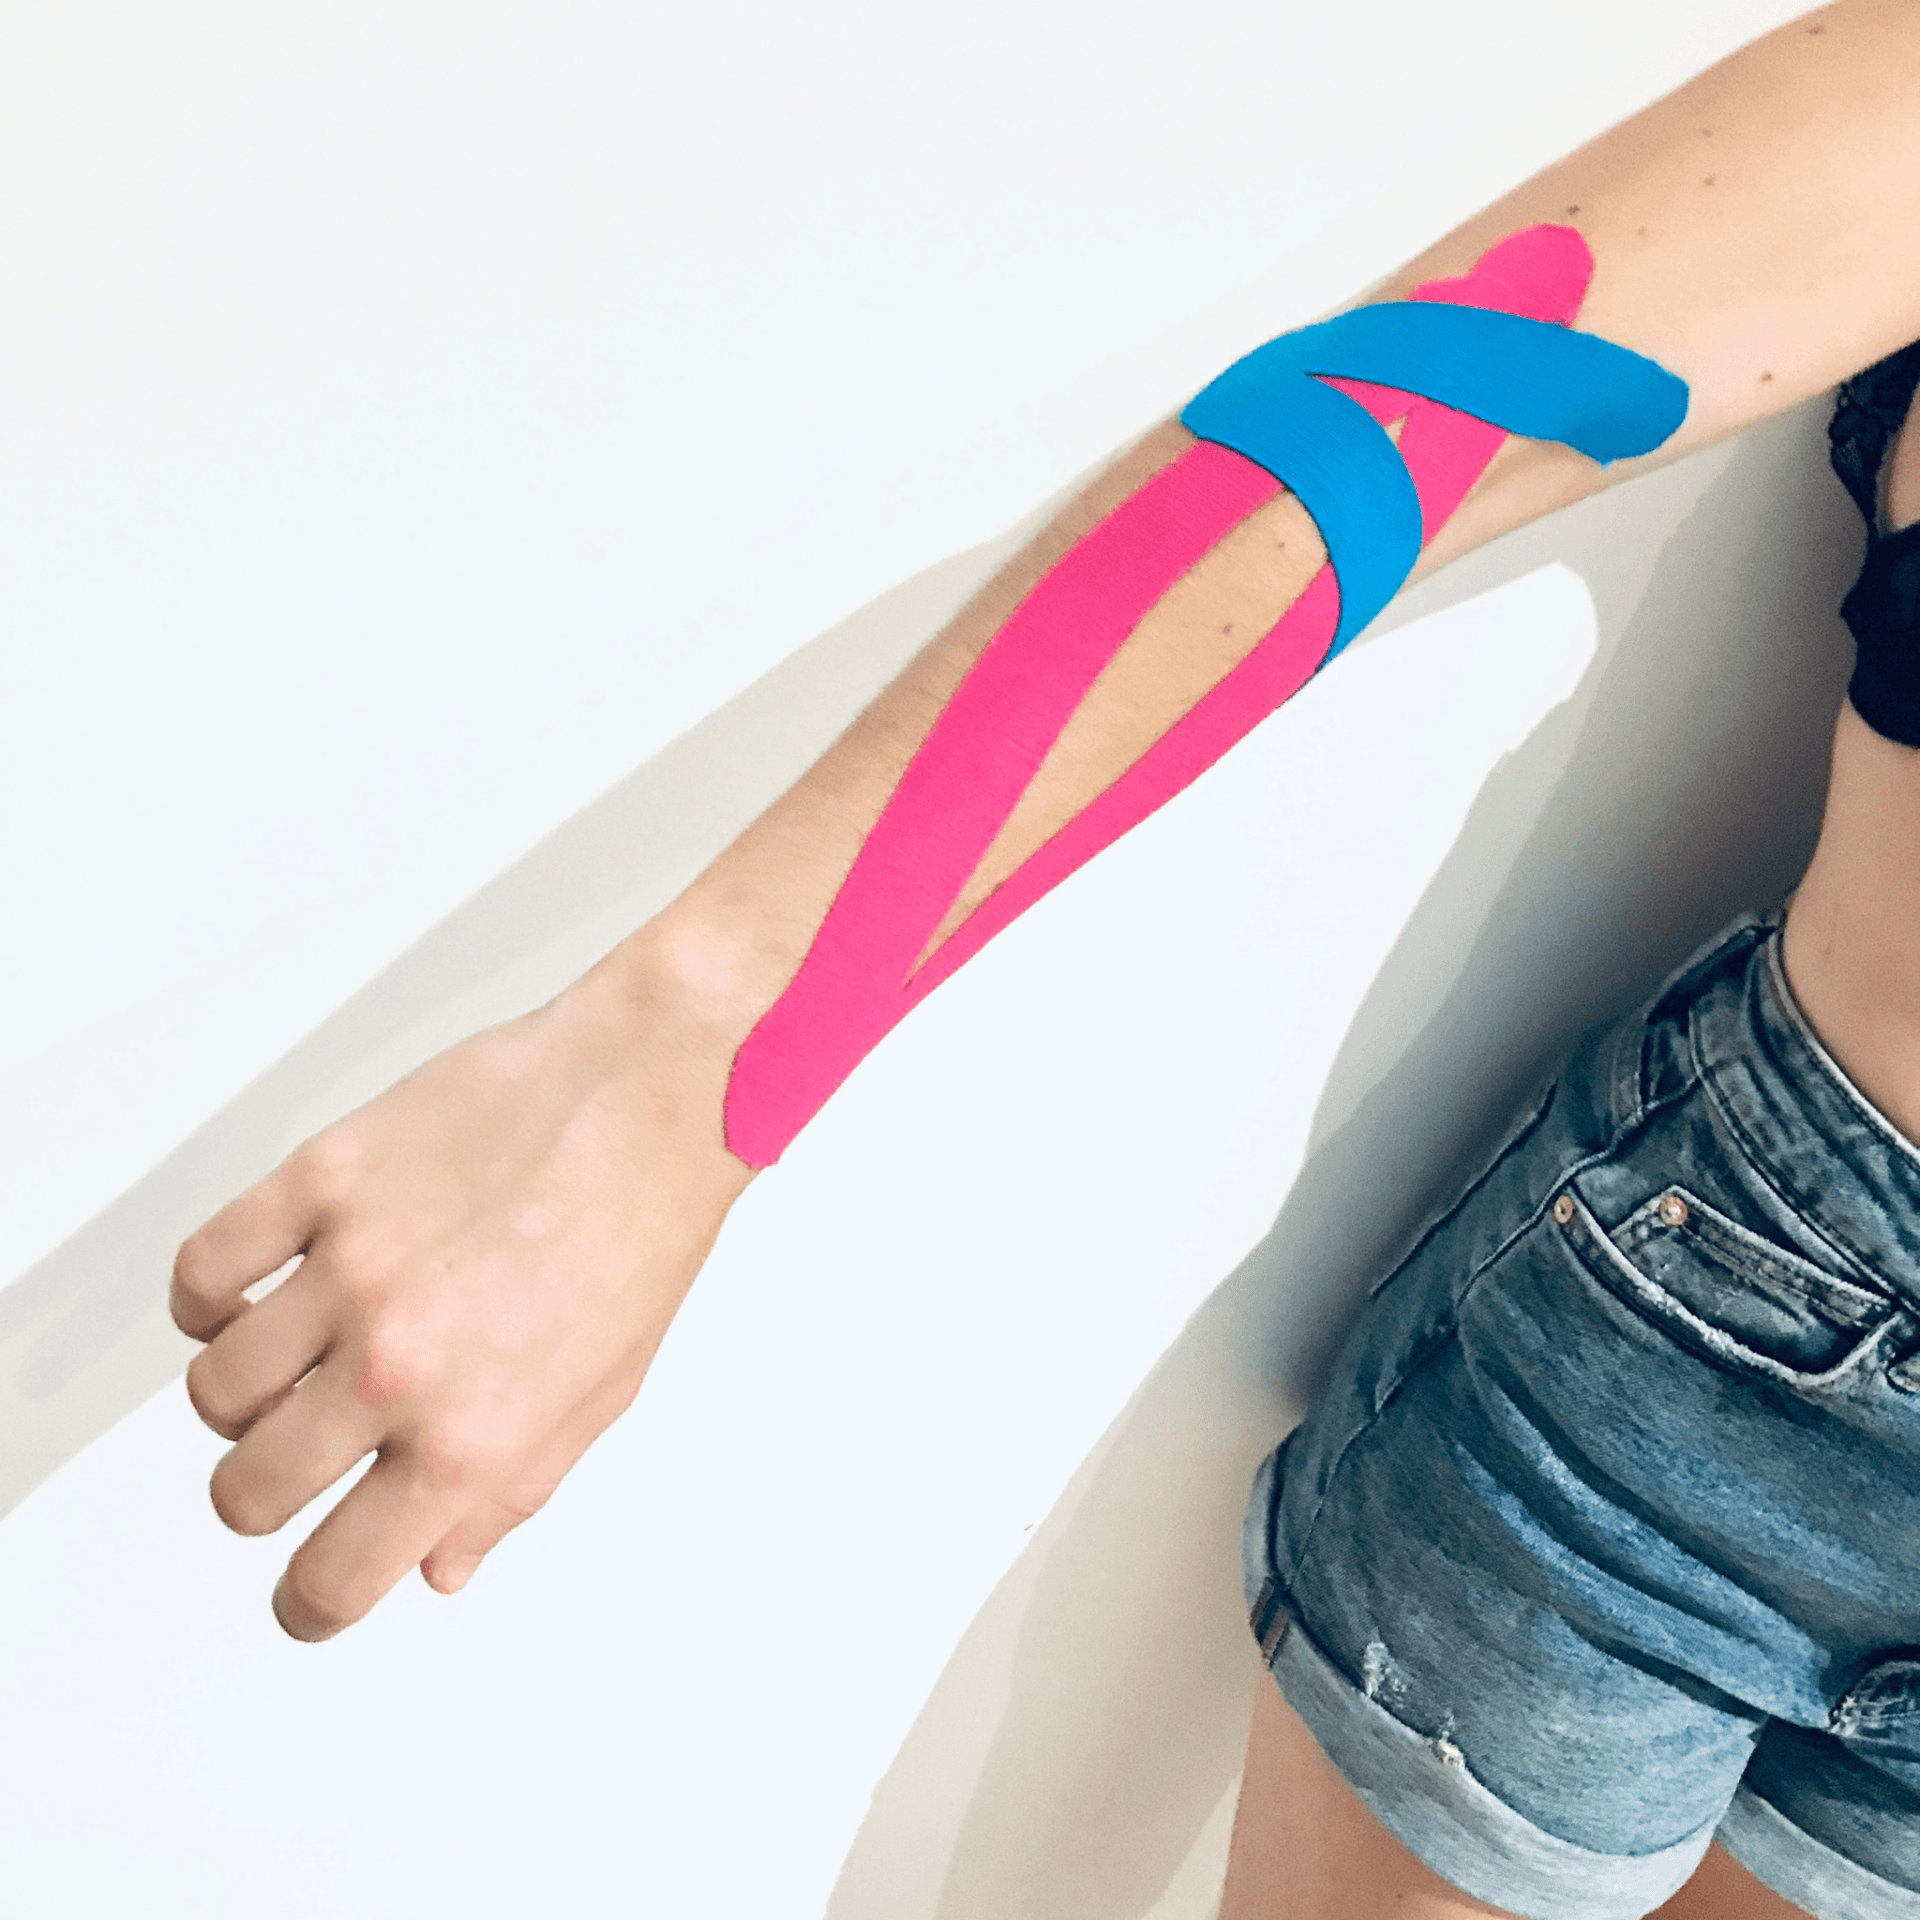

-MOVILIZACIÓN PASIVA y PASIVA-ASISTIDA: Aplicada por el fisioterapeuta para movilizar el nervio sin esfuerzo del paciente.

- MOVILIZACIÓN o DESLIZAMIENTO:

-Desde un extremo

-Desde los dos extremos (como en el ejemplo de las fotos en el que la paciente ladea la cabeza hacia el lado contrario al

que estamos tratando al tiempo que flexionamos el codo y al revés ocurre en el recorrido contrario, extendemos el

codo mientras la paciénte lleva la cabeza a su posición neutra).

Foto 1 y 2 movilización del nervio mediano desde los dos extremos